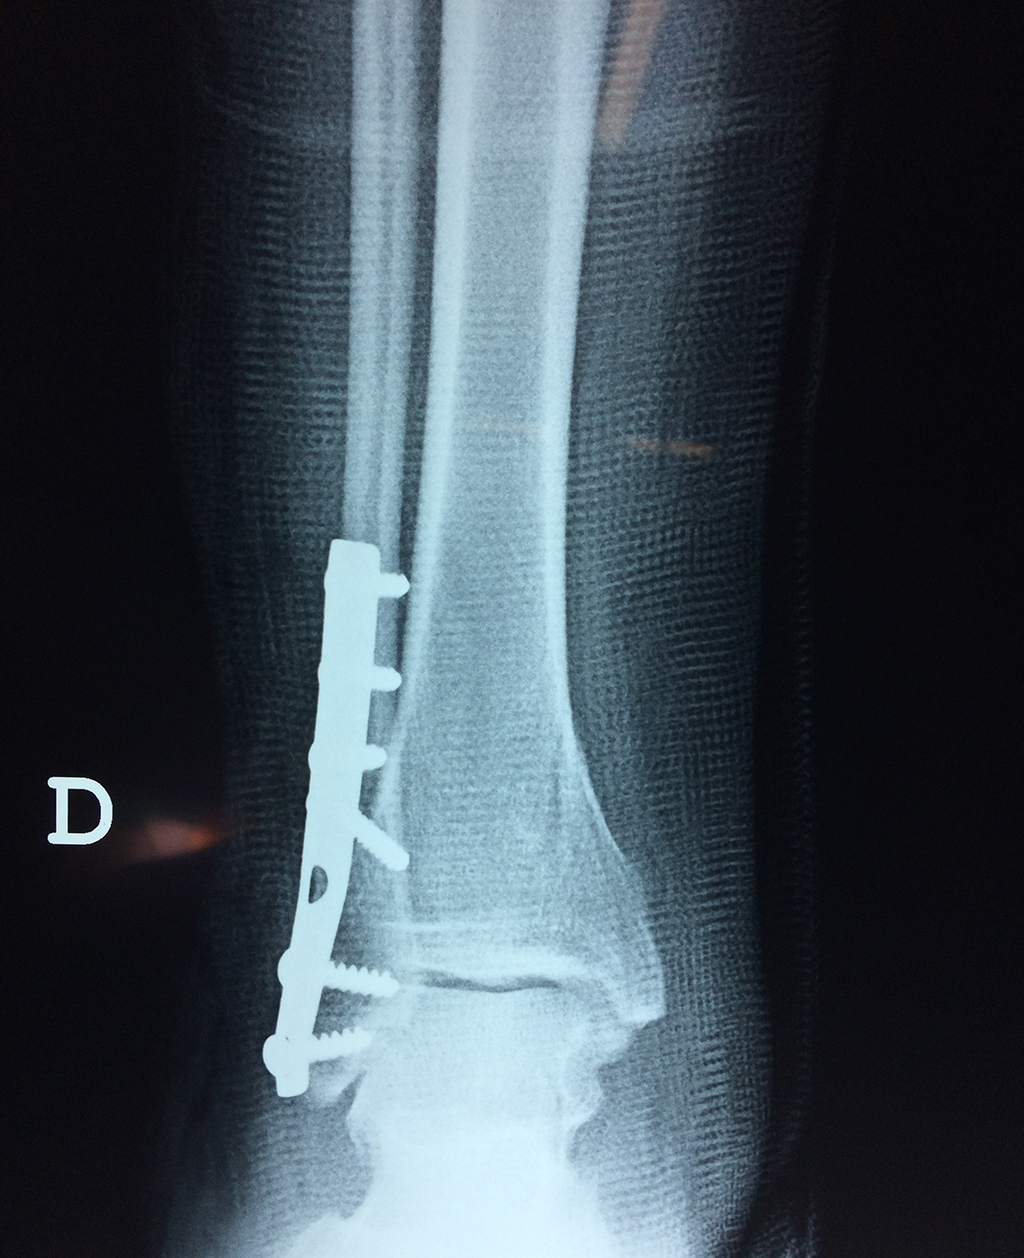

Cuando se necesita cirugía, es probable que esta implique el uso de clavijas de metal, tornillos o placas para sostener los huesos en su lugar mientras la fractura se consolida. Los elementos de soporte pueden ser temporales o permanentes.

Algunas fracturas de tobillo pueden requerir cirugía si:

- Los extremos de los huesos están desalineados entre sí (desplazados).

- La fractura se extiende hasta la articulación del tobillo (fractura intra-articular).

- Los tendones o ligamentos (tejidos que sujetan los músculos y los huesos entre sí) están rotos.

- El médico cree que sus huesos probablemente no sanen apropiadamente sin cirugía.

- El médico considera que la cirugía puede permitirle una recuperación más rápida y confiable.